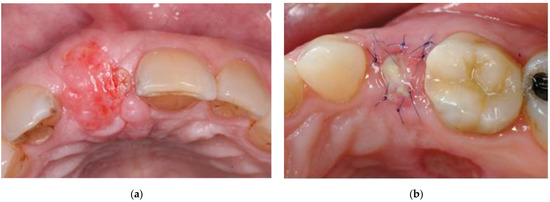

The status of the soft tissue grafts was assessed by visual inspection of the T1 photographs and was divided into 3 groups:

Group 1.

Vital: reddish tissue color indicating the graft has integration of blood supply (Figure 2a).

Group 2.

Partially vital: part of the graft presented signs of vitality (as mentioned above) and another part showed signs of necrosis, i.e., amorphous white material (Figure 2b).

Figure 2. T1 images: A vital (a) and a partially vital graft (b).